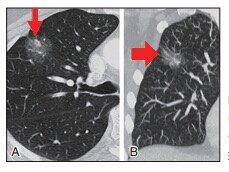

▲图8 A、B为某患者左肺上叶两幅连续的CT轴位图像,图B是随访6个月后。图A显示一非实性结节,包含几个微小泡沫样的实性密度;包括图B在内的其他层面都表现为非实结节。手术后病理证实为AIS。如果连续随访的CT图像显示病灶的实性密度随时间推移不断增加,则说明AISAB是浸润性的早期征兆